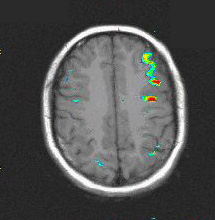

Case 2

Patient Male patient, age 13. Presurgical mapping of eloquent areas.

Paradigm Phonetic fluency

ON: Silent word generation starting with a given letter

OFF: Think of nothing

Results Strong activation in left middle and inferior frontal gyri, and left postcentral sulcus.   There is no significant activation in the right hemisphere